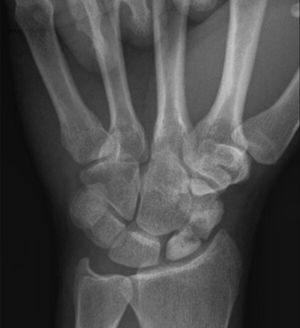

Which bone is fractured in x ray ??

First Metacarpal

Which particular bone ?

Trapezium

Nope

Scaphoid

Yeah thts correct .. most common fracture in metacarpal bone 👍👍

Os trapezoideum

Index finger(metacarpal bone proximal part)